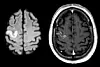

Researchers have found that people who worked more than 55 hours a week ran a 33 percent higher risk of a stroke than those working the standard 35-40 hours per week. (Photo: Microstock)

Swedish researchers found a clear link between long working hours and strokes. Strokes are caused by blood clots or haemorrhages in the brain. The recent meta-analysis was a review of 25 earlier studies covering 600,000 persons in Europe, the USA and Australia.